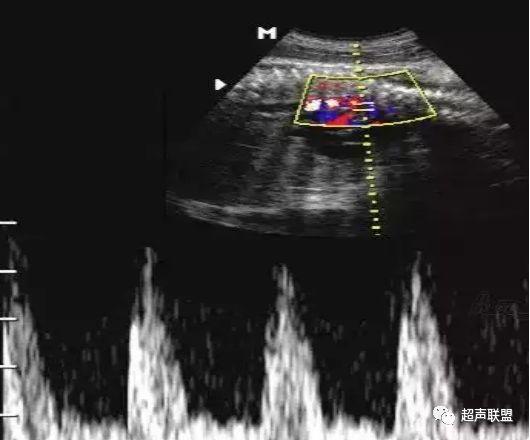

3 胎儿静脉导管

当右心负荷增大,心功能失代偿时,静脉回流受阻,静脉导管a波收缩期流速下降,血流消失甚至倒置。

4 脐静脉频谱

胎儿宫内缺氧严重时脐静脉出现搏动。

5、静脉导管:a波消失或反向(见于严重的胎儿宫内缺氧);

6、脐静脉:脐静脉搏动(见于严重的胎儿宫内缺氧);

3、静脉导管a波反向或消失;

4、脐静脉搏动。

图5 胎儿宫内正常静脉导管

图6 胎儿宫内缺氧时静脉导管a波反向

图9 脐静脉搏动